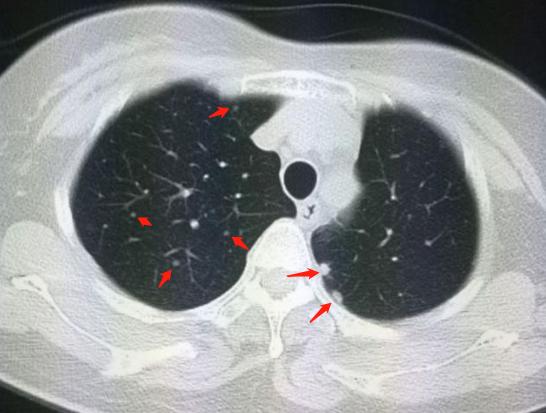

这个患者的确发生了胸膜转移和肺内多发转移:

后面这张图,箭头所示多发小结节,分别表示胸膜转移和肺内多发转移,这标志着病人失去了手术机会。